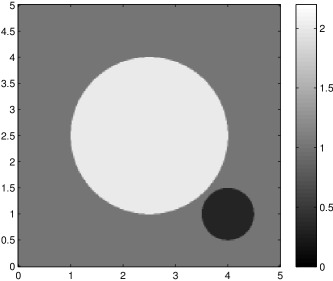

The data (see Figures 1 and 2) was generated in the diffusion model (1.2) using self-written (linear-basis) finite element code in MATLAB. For both examples, we took and used a uniform boundary condition . The simulated data were generated on a -grid and then down-sampled (by averaging) to to avoid inverse crime. After that, Gaussian noise with different intensities (standard deviations of and of the average signal value ) was added to the data.

Reconstruction results and error profiles at different noise levels can be seen in Figures 3 and 4. In both examples, the noise-free reconstructions are very accurate and contain mostly smoothing error. In the low-noise reconstructions, due to the fact that more regularization is necessary, some of the parameter variation is underestimated. In the high-noise examples, most detail in is lost since a lot of regularization is required to get reasonable results. The fine detail in can, however, still be recovered very accurately in both examples.